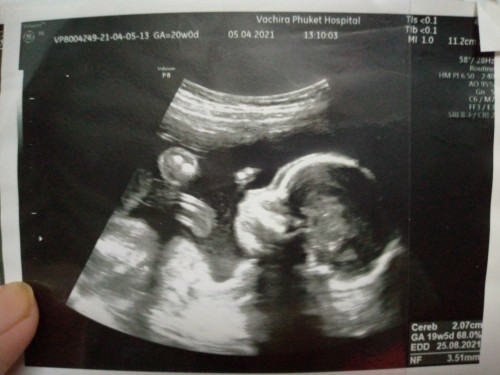

หมอบอก 80% เพศหญิงค้า.ภาพตอน19วีคค้า ตอนนี้27วีคแล้ว.🥰